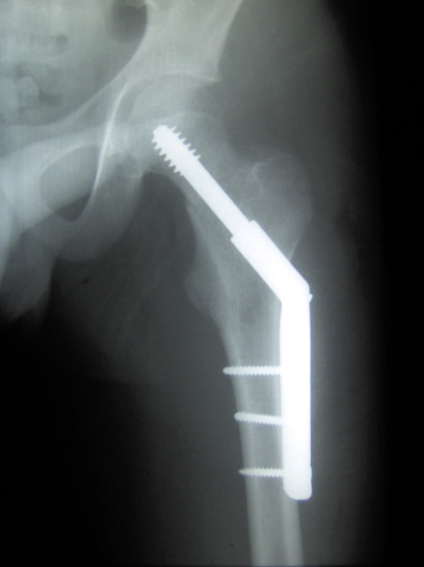

The given x-ray shows hypertrophic nonunion caused by inadequate _____

The above radiograph shows an extramedullary implant called a _____.